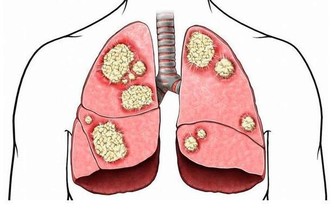

據統計,全球每年有22萬以上女性患上卵巢癌,其中約有六成患者死亡。卵巢作為女性的內生殖器官,因為位置比較深,初起癥狀輕微,所以很難被察覺,待到發現時,已經到了晚期,這時已經失去最佳治療時間。

會「隱身」的卵巢癌

卵巢在腹腔內部,常規的婦科檢查一般只能查到卵巢囊腫,進而以為它只是一種普通的婦科疾病。而且,女性生理周期紊亂也會引起卵巢囊腫,但這種囊腫在生理期后就會恢復正常。但有病變的囊腫則不然,它們經期后並不會恢復,這時需要進一步檢查,才能判斷它到底是正常的卵巢囊腫還是卵巢腫瘤。

由於檢測技術有限,目前還不能從外部確定卵巢疾病。即使用B超、彩超也只能查出個大概,再加上內分泌功能、胚胎髮育等因素的影響,使卵巢癌在早期並無明顯癥狀。